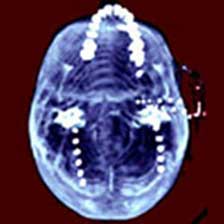

原發性癲癇避免誤診:腦囊蟲病可繼發癲癇發作,詳細詢問病史及查體,部分患者可見皮下、肌肉或眼內小結,病理檢查可發現囊蟲;血常規及腦脊液檢查可見嗜酸性細胞增多;囊蟲免疫診斷試驗其特異性抗體可為陽性;頭顱CT或MRI檢查可發現囊蟲病灶。